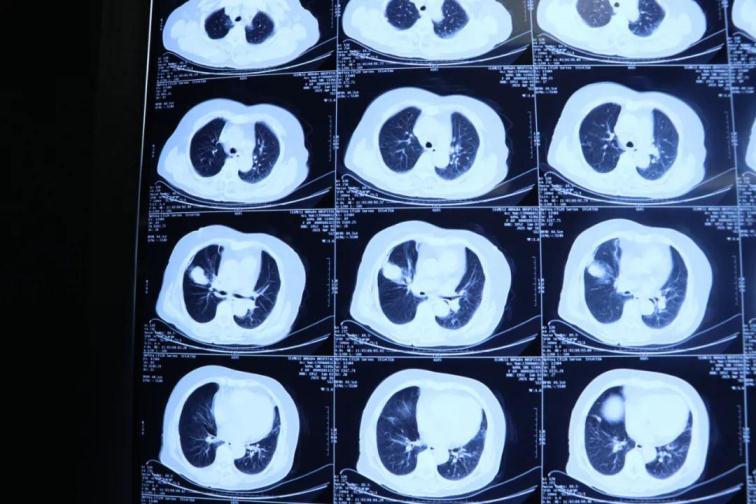

為了提高CT影像下肺腫瘤定位的精準度,術(shù)前胸外科團隊聯(lián)合CT影像科趙文禮主任和董明鑫醫(yī)師詳細研究了肺CT定位方案,采取國際上先進的CT網(wǎng)格定位法,對肺腫瘤精確定位,定位精度可達5mm以內(nèi)。經(jīng)過團隊合作充分準備后對肺癌實施了氬氦刀穿刺治療,微創(chuàng)穿刺針孔3mm,局麻鎮(zhèn)痛,分段治療40分鐘。病人全程在韋文康護士長護理團隊心肺監(jiān)測下進行,確保了手術(shù)安全。

氬氦刀治療后即刻CT評價肺腫瘤核心密度下降,手術(shù)后5天CT評價肺癌與周圍正常肺組織對比,水腫帶形成,癌組織出現(xiàn)壞死。治療取得了良好效果。遠期效果需要繼續(xù)隨訪觀察。病人手術(shù)后1周無并發(fā)癥痊愈出院。